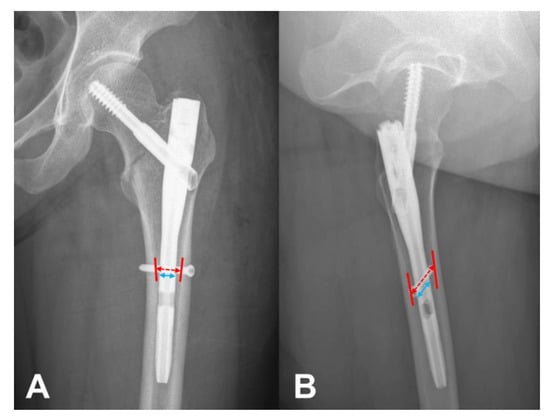

2.1. Measurement of N–C Difference